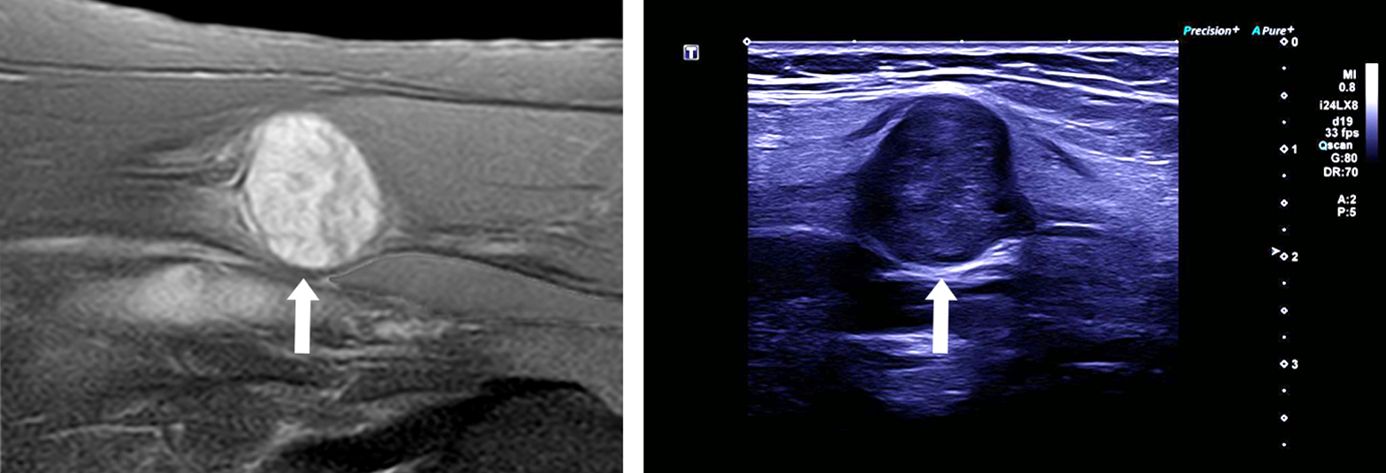

Tumoren peripherer Nerven sind seltene Erkrankungen. Typischerweise sind sie sehr langsam wachsend und gehen von den Hüllstrukturen der peripheren Nerven aus. Die beiden häufigsten Tumoren peripherer Nerven werden als Schwannome und Neurofibrome bezeichnet. In der Regel lassen sich derartige Tumoren, falls notwendig, in mikrochirurgischer Technik und unter elektrophysiologischer Kontrolle der betroffenen Nerven ohne dauerhafte Ausfallserscheinungen entfernen.

Entscheidend zur Diagnostik tragen kernspintomographische Aufnahmen (MRT) der betroffenen Körperregion bei. Auch hochauflösende Ultraschalluntersuchungen können hilfreich sein, um eine Beurteilung und Festlegung der Therapiestrategie zu ermöglichen.

Bei den meisten Tumoren handelt es sich um gutartige Tumoren, so dass bei fehlender klinischer Symptomatik und geringer Größe des Befundes auch ein abwartendes Beobachten mit regemäßigen klinischen Verlaufskontrollen und MRT-Bildgebungen als therapeutische Option erfolgen kann. Bei Beschwerden, größeren Tumoren oder bei unklaren Konstellationen kann die neurochirurgische Therapie aber notwendig werden. Die Betreuung sollte in einem spezialisierten Zentrum erfolgen.

Periphere Nerventumoren werden mithilfe eines Operationsmikroskopes freigelegt und entfernt. Zudem werden weitere Hilfsmittel wie die intraoperative Sonographie und elektrophysiologische Messungen eingesetzt, um eine möglichst vollständige Tumorentfernung zu ermöglichen, ohne eine Schädigung des betroffenen Nervens zu riskieren. Abhängig von Art und Größe des Tumors kann auch eine Teilentfernung des Nervs und ggf. anschließende Rekonstruktion erforderlich werden.